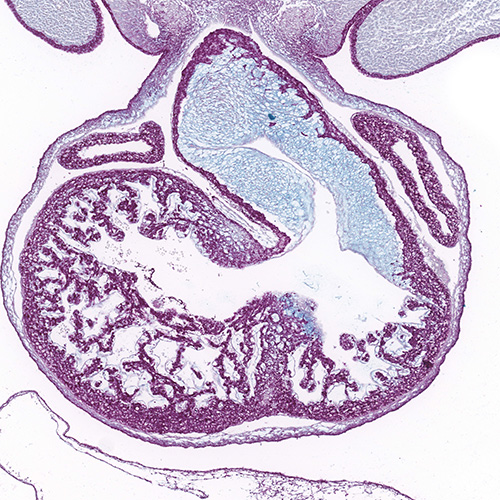

Histology Sections

NEW Kaufman's Atlas of Mouse Development Supplement in the eHistology Viewer

eHistology viewer